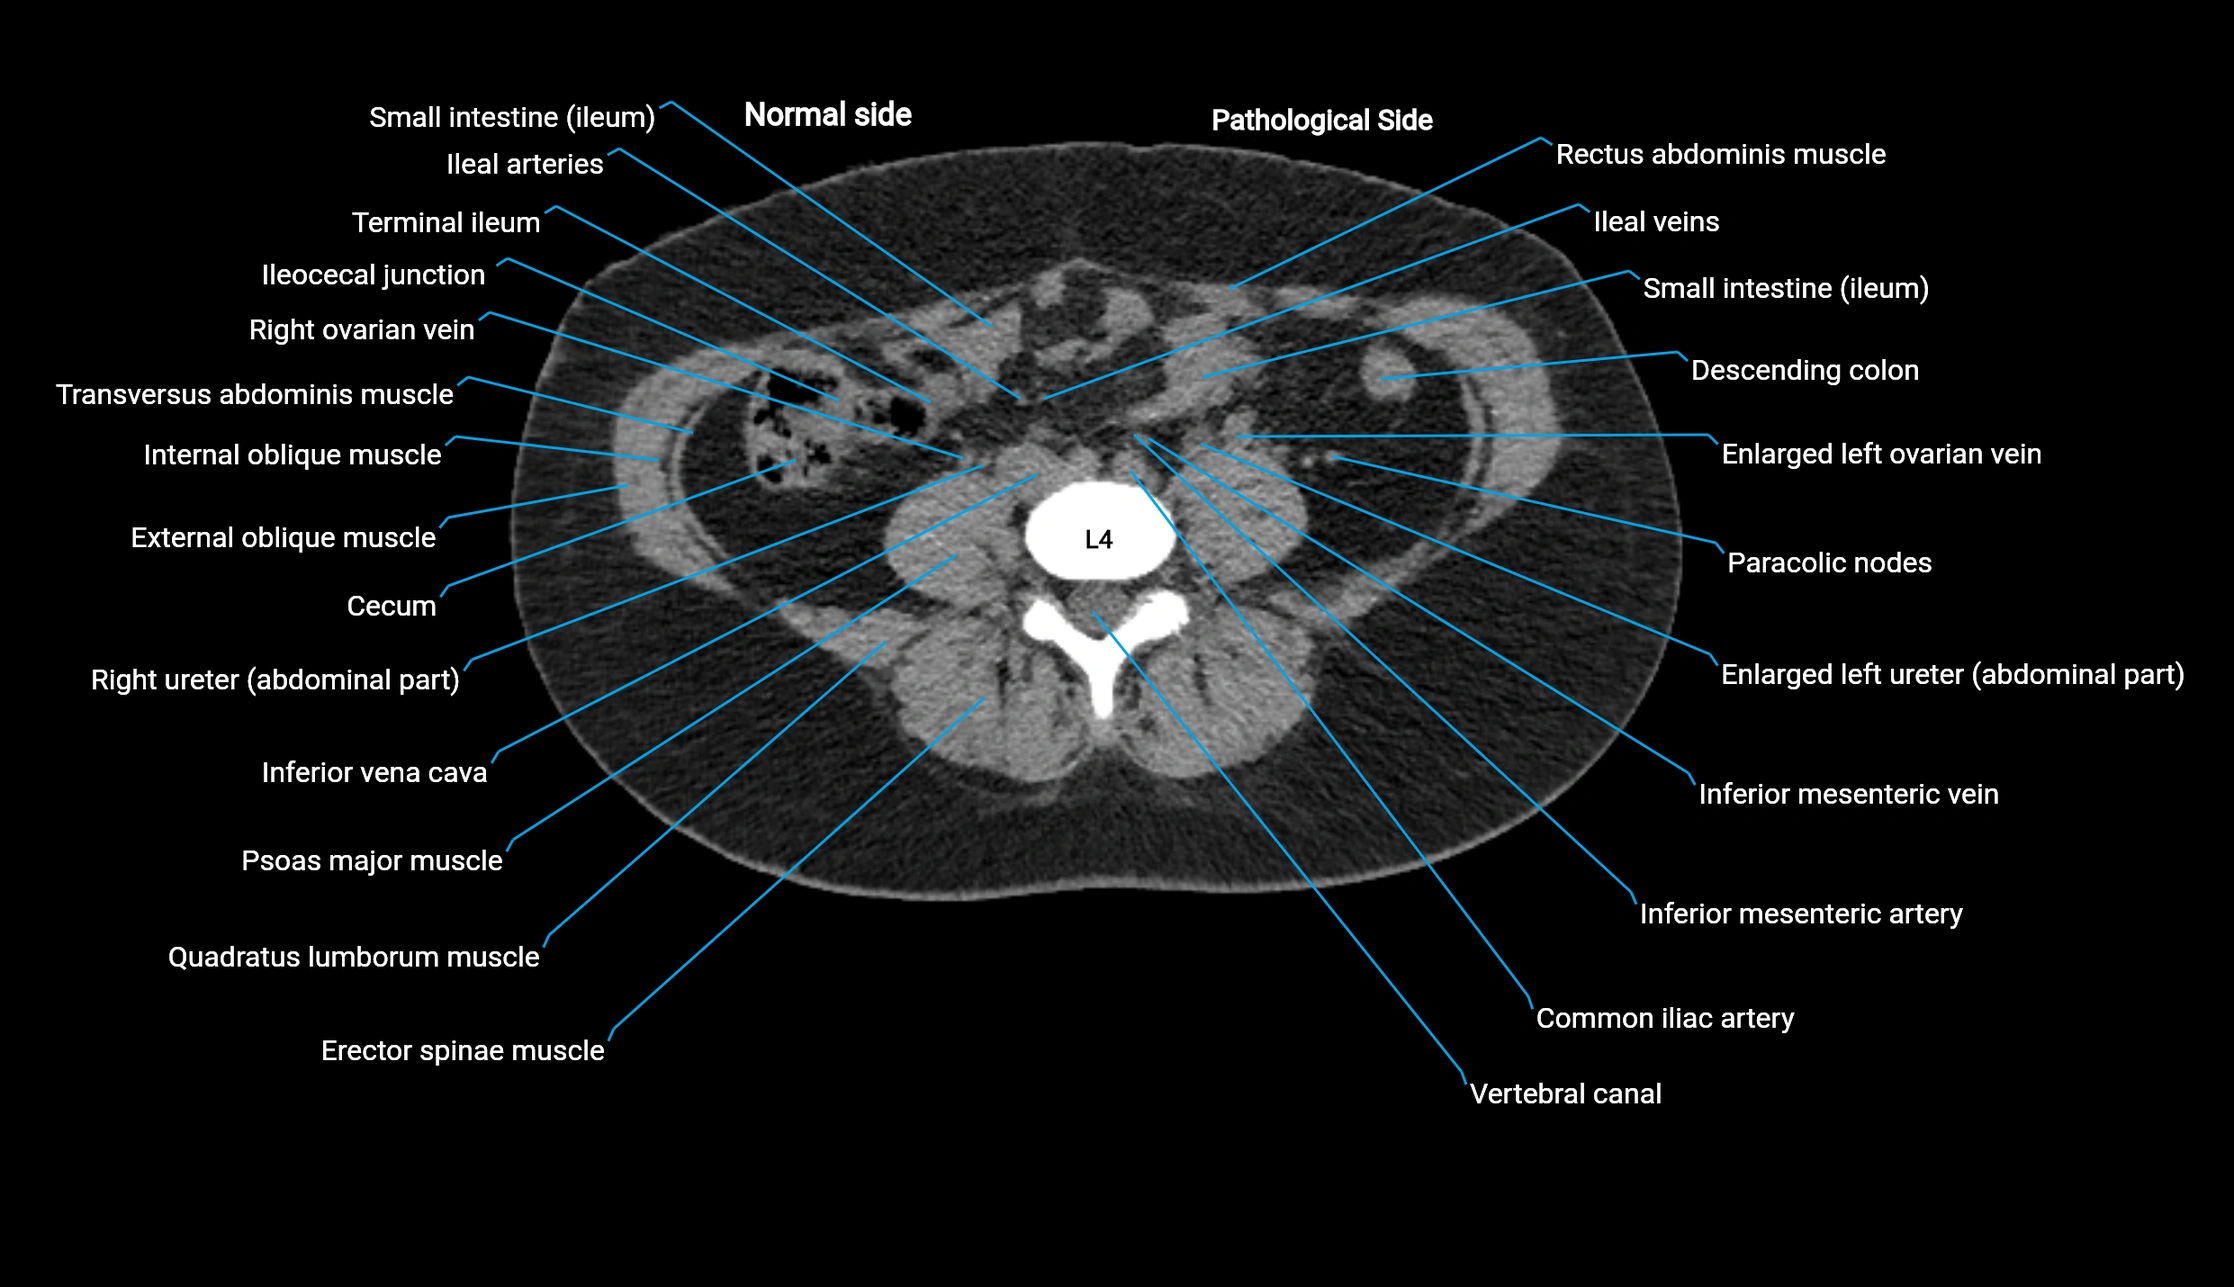

CT Appearance

Non-contrast CT:

• Demonstrates cortical bone of acetabular rim in excellent detail

• Detects fractures, dysplasia, retroversion, or bony overcoverage (pincer impingement)

• 3D reconstructions used in preoperative hip surgery planning